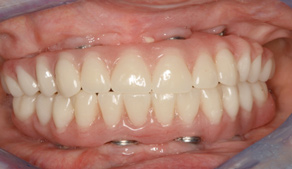

Fig 17. A three-implant fixed bridge may be an immediate-load alternative for a fixed restoration as opposed to a two-implant overdenture. In addition to significant cost reduction due to pre-manufactured components, the final long-term restoration is delivered on the day of surgery.

Figure 17

Fig 18. A three-implant fixed bridge may be an immediate-load alternative for a fixed restoration as opposed to a two-implant overdenture. In addition to significant cost reduction due to pre-manufactured components, the final long-term restoration is delivered on the day of surgery.

Figure 18

As an alternative to the relatively expensive traditional hybrid restoration that the senior population may perceive as unattainable at their age, an immediate-load all-resin provisional may often be a reasonable option as an entry-level prosthesis. This can serve for extended periods or indefinitely, and when made with a sufficient volume of resin and opposing a light occlusion such as a maxillary denture, it can offer the benefit of fixed retention at a significant reduction in expense (Figure 15 and Figure 16). Technology involving a guided approach for placing three implants universally in the same sites with pre-manufactured, one-size-fits-all bar components in the mandible can now allow placement of a final restoration in one day, again at a significantly reduced cost (Figure 17 and Figure 18).24-26 Both of these fixed options—the resin long-term provisional and the three-implant bridge—are economically comparable to the most commonly considered implant prosthesis for elderly patients, the two-implant overdenture. In contrast to the latter, however, both fixed restorations offer significant advantages in bite force, bone preservation, maintenance, and patient satisfaction that are simply unachievable with the removable implant overdenture prosthesis.27-31